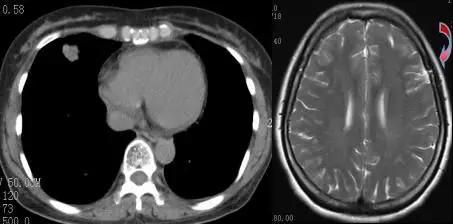

结果显示,张女士颅脑增强核磁共振提示为左侧软脑膜瘤,通过进一步的检查,竟在她的肺部发现了肿瘤病灶!

宁波市第二医院呼吸内科赵伟和主任说,张女士右中肺确定为周围型肺癌,同时伴随两肺、纵隔淋巴结、多发骨转移。导致她剧烈头痛的直接原因是脑瘤,但真正作祟的还是肺部的肿瘤。晚期肺癌、多发转移……家属怎么都想不到情况会如此严重。而张女士的症状仍在加重,剧烈的干呕症状,使得患者直呼难受。

在药物治疗症状缓解有限的情况下,呼吸内科与神经内科专家设计了“先行腰穿引*脑流**脊液,待颅高压症状改善后再行CT引导下肺穿刺活检”的治疗方案。通过脑脊液引流后,张女士的呕吐症状有明显改善。两天后,病理结果显示肺腺癌,脑脊液中也找到腺癌细胞。

检查发现,张女士肺部肿瘤仅2厘米左右,但已出现了颅脑转移,这在临床上较为少见。虽然小病灶、大转移并不多见,但影像检查中,她肺部的病灶已呈现高密度影。“在影像学上,病灶最初为半透明的磨玻璃样,一般需要半年至一年时间,病情逐渐进展才会呈实质性病灶。”赵伟和主任提到。